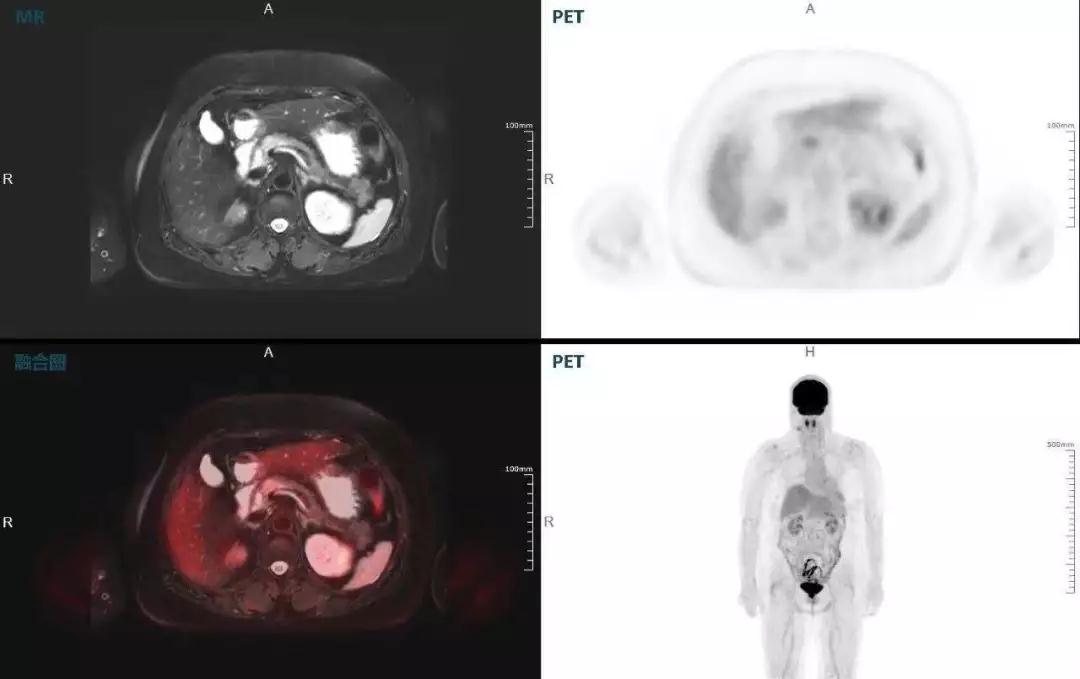

中山醫(yī)院核醫(yī)學(xué)科在臨床實踐中發(fā)現(xiàn),基于聯(lián)影“時空一體”超清TOF PET/MR,不僅解剖信息和代謝信息能夠完美融合呈現(xiàn),同時精細(xì)展示局部病灶與周圍組織的復(fù)雜關(guān)系,并能全盤檢測病灶的全身轉(zhuǎn)移,為醫(yī)生臨床診斷提供更豐富信息。

(胰腺腫瘤,MR顯示胰腺體部信號異常,PET顯示稍高攝取,結(jié)構(gòu)改變和功能異常提示胰腺MT可能大。)